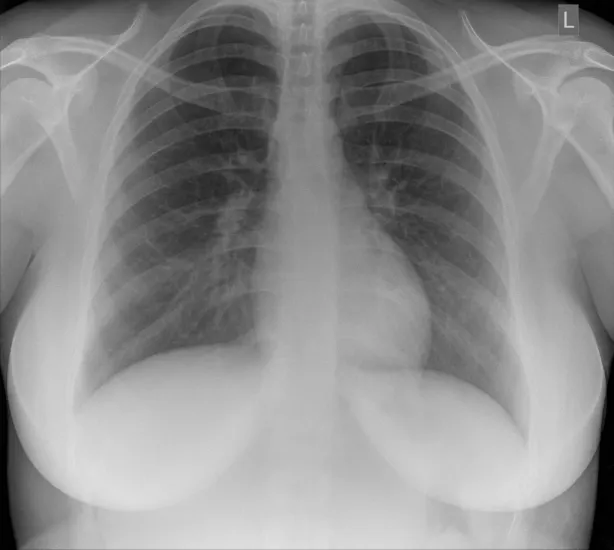

This script loads a pre-trained U-Net Keras model for lung segmentation, processes a test image, predicts the segmented lung region, and displays both the original image and the predicted mask.

It resizes the image, normalizes pixel values, applies a binary threshold to the mask, and visualizes the results using OpenCV.

The Unet Tensorflow result :